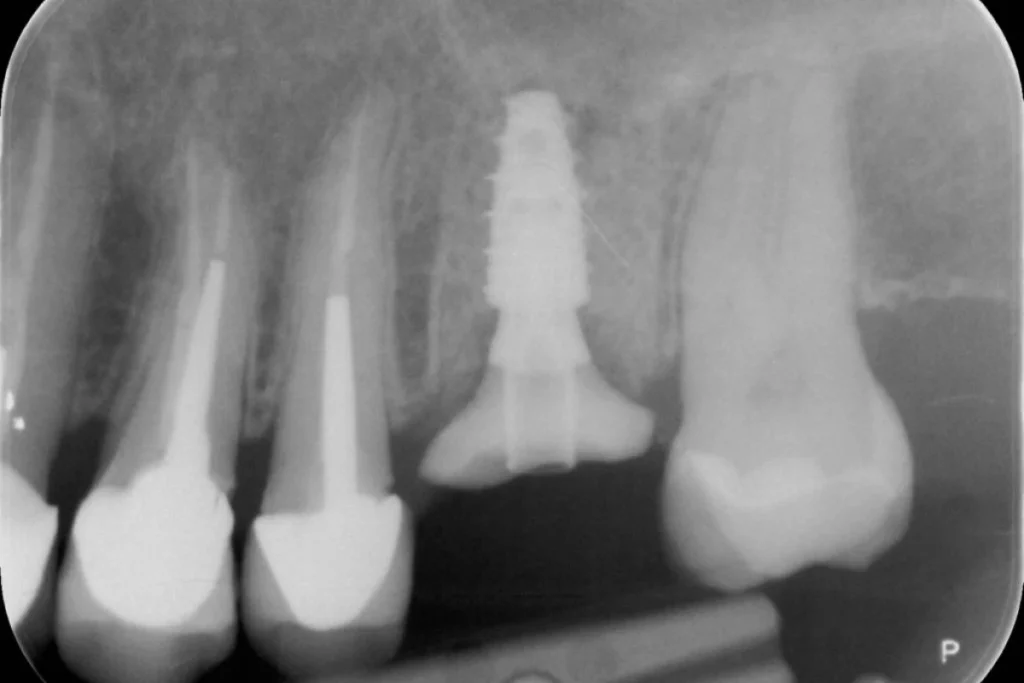

Mr C. 40 ans vient nous consulter pour une visite de routine. L’examen clinique et met en évidence un infection sous une dent couronnée il y plusieurs années par un confrère. Le scanner réalisé au cabinet confirme la nécessité d’extraire cette dent et nous décidons de réaliser un protocole d’extraction implantation et mise en esthétique immédiate.

En clair, nous réalisons l’extraction de la dent, la mise en place de la racine artificielle ou implant et la fabrication d’une couronne provisoire en résine le tout lors de la même séance. Le patient repart du cabinet avec toutes ses dents!

Dans le cas présent, nous avons même pu répondre à la demande esthétique du patient en symétrisant son incisive latérale droite avec celle de gauche. L’intervention est réalisée sous anesthésie locale ce qui la rend parfaitement indolore.

Ce type de protocole est réalisé systématiquement au cabinet lorsque la situation nous le permet afin d’éviter à nos patients la galère d’un appareil provisoire amovible pour remplacer la dent absente. En contrepartie, le patient s’engage à respecter nos recommandations post opératoires pendant les semaines qui suivent l’intervention.